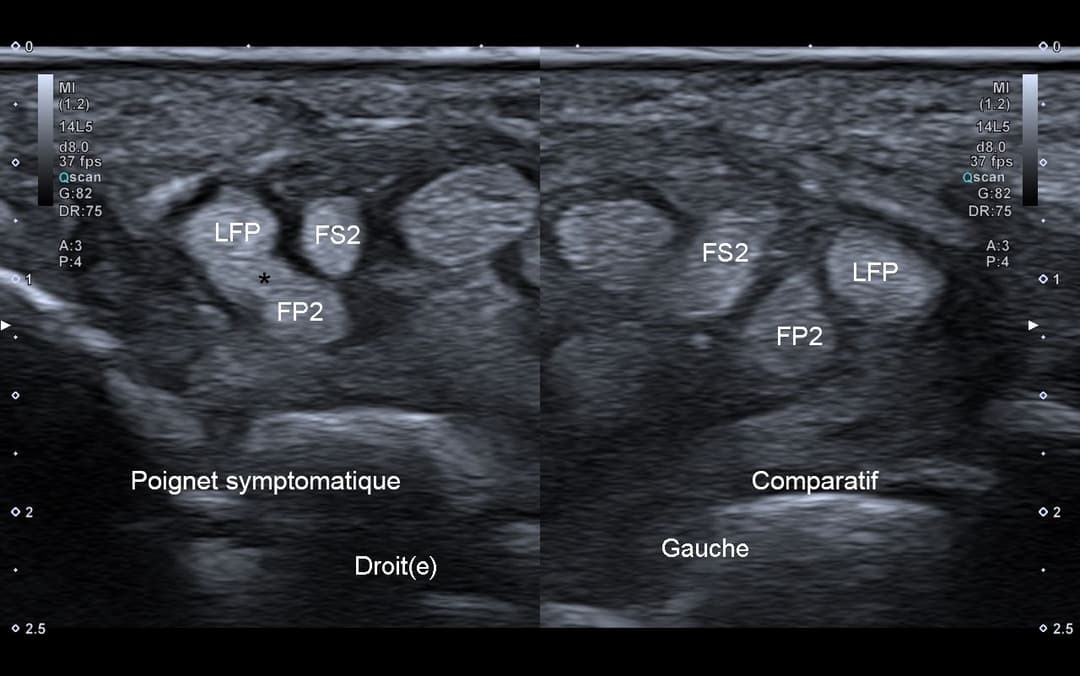

L'échographie révèle une bride tendineuse (astérisque) entre le tendon du long fléchisseur du pouce (LFP) et le tendon du fléchisseur profond (FP2) du deuxième doigt, au sein du canal carpien.

Coupe axiale comparative du poignet au niveau du canal carpien